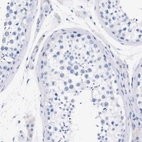

Immunohistochemistry analysis in human cerebral cortex and liver tissues using HPA014518 antibody. Corresponding P2RY12 RNA-seq data are presented for the same tissues.

The Anti‑P2RY12 antibody (HPA014518) is a highly specific marker for microglia, the brain’s resident immune cells. P2RY12 is uniquely enriched in homeostatic microglia, making this antibody an ideal choice for precise microglial identification in healthy and diseased CNS tissue.